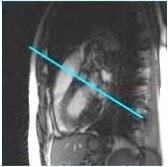

2. From the right ventricular outflow tract view, prescribe (blue line indicates graphic location) and acquire a pulmonary valve view.

Figure 2. Prescribe pulmonary valve view